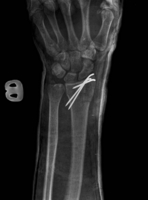

Van valakinek tapasztalata csuklósérüléssel kapcsolatban? Az orsócsontom tört 2 helyen és a sajkacsontom. 3 szeggel rögzítették az orsót, a sajkát nem kellett.

Minden érdekel, gyógyulás, rehab, erősítés, majdani védelem, orvosok, kórházak. Esztergomban műtötték, dr. Kőváry Tamás. Műtötte már Borkát, meg Léczet, elméletileg van esély, hogy teljesen helyrejön...